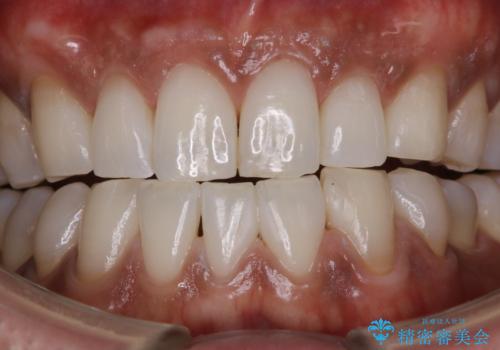

前歯の着色をPMTCできれいに